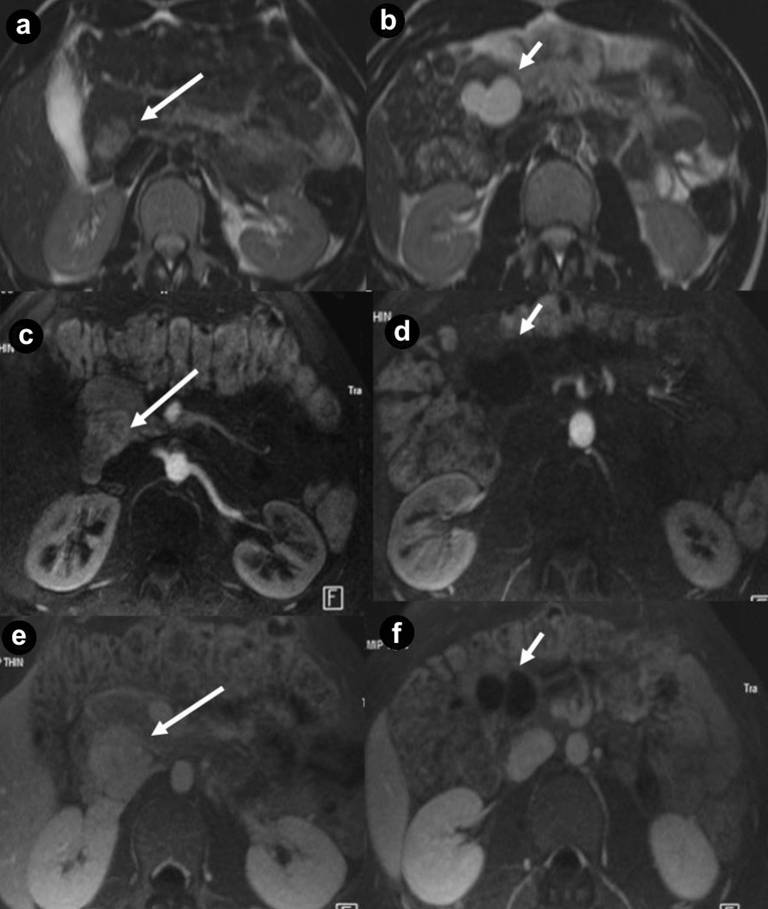

Figure 3. Pancreatic non functioning neuroendocrine tumor and pancreatic serous cystadenoma in the same patient: asymptomatic 24-year-old man. Axial (a. b.) T2-weighted MR images, axial 3D volumetric gradient-echo T1-weighted fat suppressed images after intravenous contrast medium administration during arterial pancreatic (c. d.) and portal venous (e. f.) phases of contrastographic dynamic study. In pancreatic head a solid mass (a. arrow), heterogeneously hyperintense on T2-weighted MR images (a.) with homogeneous enhancement after intravenous contrast medium administration during arterial pancreatic phase of contrastographic dynamic study (c.), without wash-out in portal venous phase (e.) is present. In pancreatic head a cystic parenchymal lesion (short arrow), more hyperintense than solid mass, with fluid signal intensity on T2-weighted MR images (b.), without enhancement after intravenous contrast medium administration during arterial pancreatic (d.), and portal venous phases (f.), is visible. Inside the cystic lesion a septa is recognizable. Pancreaticoduodenectomy with Whipple procedure was performed. Histological specimen showed the presence of pancreatic macrocystic serous cystadenoma and non functioning neuroendocrine tumor of pancreatic head. |

Figure 4. Pancreatic diffuse microcystic serous cystadenoma and pancreatic non functioning neuroendocrine tumor in the same patient. A 24-year-old woman with VHL disease and symptoms of pancreatic exocrine insufficiency. Axial (a. b.) and coronal (c.) T2-weighted MR images, MR cholangiopancreatography (d.) and axial 3D volumetric gradient-echo T1-weighted fat suppressed images after intravenous contrast medium administration during arterial pancreatic (e.) and portal venous (f.) phases of contrastographic dynamic study. Pancreatic gland is enlarged and parenchyma is completely replaced by multiple, lobulated fluid cysts, hyperintense on T2-weighted MR images, with a “bunch of grapes” pattern (a. b. c. d.). In the pancreatic head, a round solid mass (arrow), with the signal intensity less high than other pancreatic cysts on T2-weighted MR images and homogeneous enhancement after intravenous contrast medium administration during arterial pancreatic phase (e.), with low wash-out in portal venous (f.) phase, is present. Multiple bilateral renal cystic lesions and large complex mass on the left kidney (short arrow), with fluid signal intensity, multiple solid septa and heterogeneous enhancement after intravenous contrast medium administration during arterial (e.) and portal venous (f.) phases, are detected. Total pancreatectomy and surgical enucleation of the left renal mass were performed. Histological specimen showed the presence of pancreatic diffuse serous cystadenoma, non functioning neuroendocrine tumors of pancreatic head and cystic renal cell carcinoma of left kidney. |

Figure 5. Pancreatic diffuse microcystic serous cystadenoma and pancreatic non functioning neuroendocrine tumor in the same patient. Asymptomatic 34-year-old woman, member of family affected to VHL disease. Axial (a.) and coronal (b.) T2-weighted MR images, MR cholangiopancreatography (c.) and axial 3D volumetric gradient-echo T1-weighted fat suppressed images after intravenous contrast medium administration during arterial pancreatic (d.), portal venous (e.) and delayed (f.) phases of contrastographic dynamic study. Pancreatic gland is enlarged and parenchyma is completely replaced by multiple, lobulated fluid cysts, hyperintense on T2-weighted MR images, with a “bunch of grapes” pattern (a. b. c.). The wall of cystic lesions and septa inside them shows enhancement after intravenous contrast medium administration during arterial pancreatic (d.), portal venous (e.) and delayed (f.) phases. In pancreatic head and neck, some cysts result so small and so numerous as they show lower signal intensity on T2-weighted MR images compare to fluid lesions and appear at MR imaging like solid mass (short arrow). In the pancreatic body, a round solid mass (arrows), with the signal intensity less high than the other pancreatic cysts on T2-weighted MR images and homogeneous enhancement after intravenous contrast medium administration during arterial pancreatic phase (d.) with low wash-out during portal venous phase (e.) but hypointense on delayed (f.) phase, is present. Multiple bilateral renal fluid cysts are detected. Splenopancreatectomy was performed. Histological specimen showed the presence of pancreatic diffuse serous cystadenoma and non functioning neuroendocrine tumors of pancreatic body-tail. |

Thirty-four pancreatic lesions were found in the 23 patients. In qualitative analysis, the MR imaging findings were: 6 (26.1%) unilocular fluid cystic lesions (Figure 1abc): 3 (13.0%) in pancreatic head, 3 (13.0%) in pancreatic body-tail; 11 (47.8%) serous micro- or micro/macro-cystic cystadenomas (Figures 1def, 4, and 5): 1 (4.3%) in pancreatic head, 2 (8.7%) in pancreatic body-tail (Figure 1), 8 (34.8%) diffuse (Figures 4 and 5); 8 (34.8%) neuroendocrine solid tumors: all of them non-functioning NET and hypervascular during arterial pancreatic phase of contrastographic dynamic study (Figures 2, 3, 4, and 5), 4 (17.4%) at pancreatic head (Figures 2ab; 3ace, and 4), 4 (17.4%) at pancreatic body-tail (Figures 2cd and 5); 1 (4.3%) cystic non-functioning NET, diffuse in all pancreatic gland (Figure 6); in 4 (17.4%) cases association of non-functioning NET and pancreatic cystic lesions (3 cases of association of non-functioning NET and serous cystadenoma (13.0%); 1 case of association of non-functioning NET and pancreatic simple cystic lesion (4.3%)) were present (Figures 4 and 5). Vascular invasion was not detected in any patients.

Microcystic serous cystadenomas or micro/macro-cystic serous cystadenoma may be diffuse in all pancreatic gland [22, 23]. In this case the pancreas appears at MR imaging [23] markedly enlarged, with parenchyma almost completely replaced by innumerable cysts, with “bunch of grapes” pattern, present only in these patients (Figures 5 and 6).

To obtain pathological specimen and histological confirmation of MR imaging findings we retrospectively evaluated symptomatic patients only (13 out of 23; all of them submitted to surgical procedure) and we do not know the pathological specimen of the remaining patients not submitted to surgical procedure(10 out of 23). It can explain the high frequency of serous cystadenoma in our series of VHL patients, differently from other study cases. The average maximum diameter of these lesions was 56.6 mm and 34.8% of these cases were diffuse in all pancreatic gland (Figures 4 and 5); 8.7% were localized at pancreatic body-tail (Figure 1def) and 4.3% were localized at pancreatic head (Figure 3bdf). According to Agarwal et al. [22], in 13.0% of our cases, the serous cystadenoma (all of them diffuse in all pancreatic gland) were associated to hypervascular solid neuroendocrine tumors (Figures 4 and 5).

They show intense and early enhancement after gadolinium-chelates injection during MR dynamic study, resulting hyperintense masses at enhanced pancreatic phase of MR study (Figures 2bd, 3c, 4e, and 5d), with a reduced or moderate reduced or non reduced signal intensity in successive venous and delayed phases of dynamic study because of wash-out, or low wash-out, or no wash-out of gadolinium contrast medium, respectively.